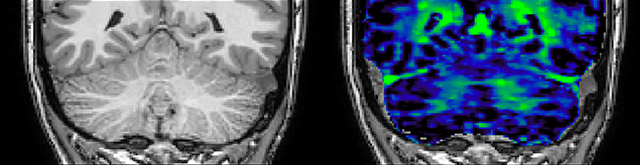

At UBC, a lot of the MS-related work focuses on myelin imaging. “We're born with very little myelin and that increases as the brain grows, which is important for nerve signal propagation. Multiple sclerosis on the other hand, degenerates the myelin with the opposite effect. So, myelin has a really important role in brain function, and having a tool that measures myelin can be extremely useful, we feel,” says Dr. MacKay.

Myelin water imaging (MWI) is a breakthrough technique that was pioneered at UBC for measuring myelin content in the brain, in vivo. “Because the T2 time of water in myelin is much shorter than the T2 of water in the intraand extracellular spaces, we can separate out the myelin water signal.”

The techniques for measuring myelin have changed a lot over the years. “Since we are using the Elition, our myelin water images are much better. We're now acquiring 1 x 2 x 5 mm voxels and displaying at 1 x 1 x 2.5 mm. For a whole brain we can now measure the fraction of water in the myelin component in only about five or six minutes,” Dr. MacKay says.

T1 - Weighted, Myelin Water Fraction Superimposed

Spinal cord coverage

Smaller, more isotropic voxels

Excellent detail in quantitative maps

Images courtesy of Adam Dvorak, Department of Physics and Astronomy, University of British Columbia